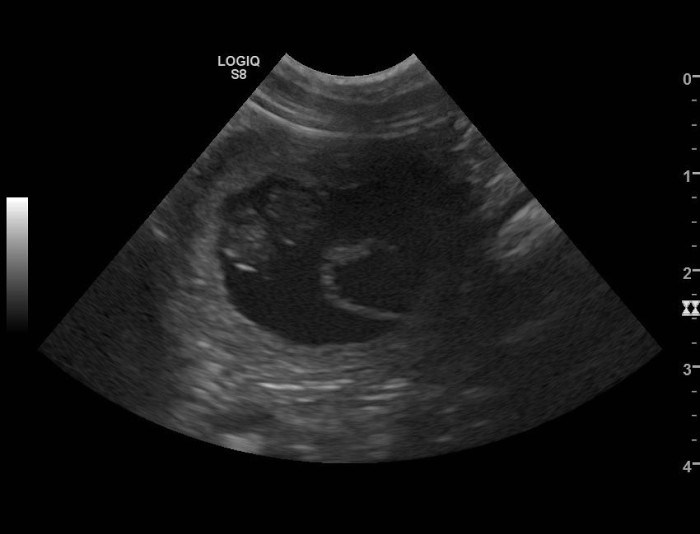

Quenie war zum Decken bei Tikki. Wie das Ultraschallbild zeigt, ist sie jetzt schwanger. |